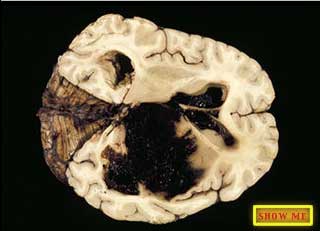

Can you see the areas that are filled with blood?